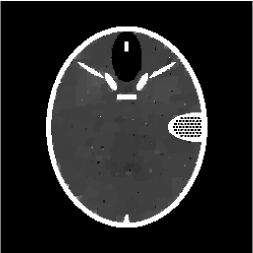

Figures 4 and 5 present visual reconstruction results of the SL phantom and the FB phantom, respectively, both under high additive Gaussian noise (). In particular, Figure 4 is to recover the SL phantom using 7 radial lines. The model has severe streaking artifacts due to this extremely small number of data obtained on the radial lines. The minimization on the gradient yields significant improvements over the baseline model (TV). The proposed algorithm outperforms the previous ADMM approach at the outer ring and boundaries of the three middle oval shapes, which are more obvious in the difference map to the ground truth. On the other hand, the FB phantom has finer structures and lower image contrast compared to the SL phantom. As a result, it requires 13 radial lines for a reasonable reconstruction. As we observe in Figure 5, the overall geometric shapes are preserved. At the same time, many speckle artifacts appear in the reconstructed images by no matter which algorithm is used.